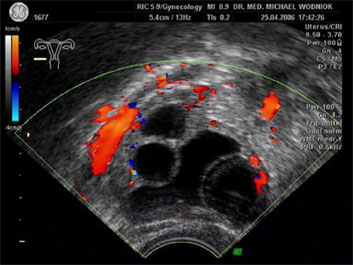

Hochauflösende Ultraschalluntersuchungen in Kombination mit der 3D-4D Technik werden in unserer Praxis routinemäßig durchgeführt. Dabei werden im Rahmen der Vorsorgeuntersuchung, sowie bei reinen vorsorglichen Ultraschalluntersuchungen auf Wunsch, auffällige Tastbefunde und noch unentdeckte Befunde weiter sonografisch abgeklärt. Bei zweifelhaften Befunden der Brüstdrüsen oder von Organen der inneren Genitalien kann der zusätzliche Einsatz der Farbdopplertechnik sehr hilfreich sein. Dabei stellt diese Technik bildlich sehr genau den Blutfluss, die Flussgeschwindigkeit, den Blutflusswiderstand sowie die Blutflussrichtung aller Blutgefässe dar. Die Interpretation dieser Ergebnisse fließt als zusätzlicher „Marker“ in die Entscheidung für das weitere klinische Vorgehen ein. Ein zunächst als völlig unauffällig eingestufter Ultraschallbefund eines zystischen Befundes im Eierstock wird bei einem unerwartet auffälligen Blutfluss an der inneren Zystenwand eine zeitnahe weitere Abklärung zu Folge haben. ![]() ![]() ![]() ![]() |